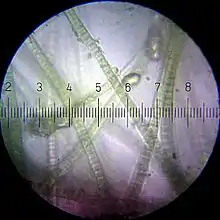

Axonal transport, also called axoplasmic transport, is a cell process not only responsible to the movement of protein and membrane to its axon, but also responsible to the movement of molecules that destined for degradation from the axon back to the cell body. Movement toward the cell body is called retrograde transport; movement toward the synapse is called anterograde transport.

Axonal transport is essential to neuron cell growth and survival. Axon of neuron is 1,000 or 10,000 times the length of the cell body, but contains no ribosomes, which means that it is unable to produce protein. All proteins and membrane must synthesize proteins in neuronal cell body or neuron cell dendrite, and then transport back to the axon. The motor protein kinesin is a motor protein used during anterograde processes while dynein is used in retrograde processes .

Vesicular cargoes move 50-400 mm/day whereas proteins move less than 8 mm/day.